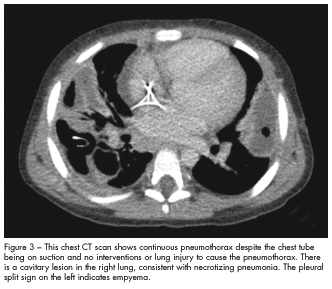

The hospital course was complicated by bilateral pleural effusions with empyema that required bilateral chest tube placement. Repeated video-assisted thoracoscopic surgery with decortication revealed massive necrotizing pneumonitis with abscesses on pathology tissue examination (Figure 2). The patient’s condition was further complicated by a bronchopleural fistula in the right lung that was managed conservatively (Figure 3). He received 21 days of vancomycin and 28 days of ceftriaxone. After 34 days in hospital, he was discharged with instructions to complete high-dose oral amoxicillin/clavulanate at home.